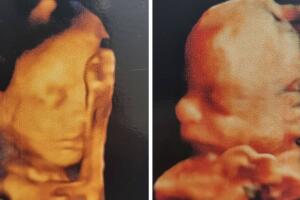

La actriz ya mostró a sus mellizos

En septiembre, Claudia enseñó en sus historias de Instagram una ecografía de sus bebés, donde todavía no se distinguían a la perfección sus rasgos, pero el 22 de noviembre compartió unas imágenes donde ya se aprecian las narices, manos y bocas de los mellizos.

“Gracias a Dios todo va perfecto con su desarrollo, ya pesan medio kilogramo (1.1 libras) cada uno, pero mi espalda los siente como si pesaran mucho más”, escribió la intérprete junto a las ecografías.